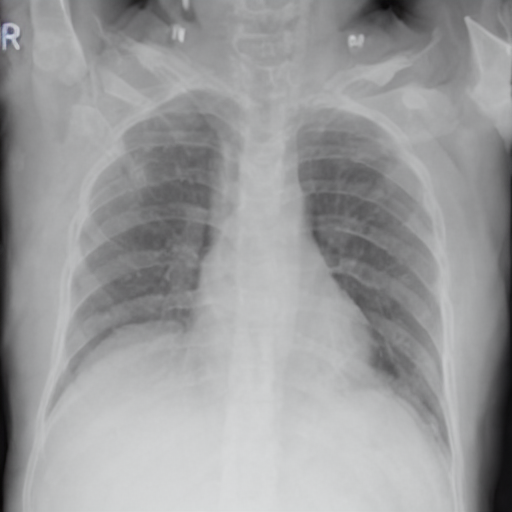

To evaluate this in more detail we examine a less localised condition: Cardiomegaly.

Zero-shot evaluation: Cardiomegaly

The disease cardiomegaly (enlargement of the heart) was not present in the training data; to evaluate zero shot induction in this context, we take real images from the small version of the Chexpert[52] dataset (from https://www.kaggle.com/datasets/ashery/chexpert). Thus, 8060 images of positively identified cases of cardiomegaly were used as the reference image set for real cardiomegaly. Correspondingly, for each of the healthy images from the COVID 19 database, an induced version was generated by the model with the prompt “Cardiomegaly". FID scores between the real cases of cardiomegaly from the Chexpert dataset and the generated images are given in Table 4.

The FID scores in Table 4 indicate that the generated cardiomegaly images do not have a large distance (using the 275.0 baseline of the Roentgen[30] study) from the real images from which they were generated, suggesting appropriate perturbations were made and the generations were reasonably close to the real cardiomegaly set from the Chexpert dataset.

Interestingly, while generation across different settings of the visual diffusion hyperparameters Strength & Guidance-scale did not have a very significant difference on FID scores evaluated across the full range of image sets, visual differences for individual images could be more significant, as highlighted in Figure 5 for two different settings of the respective hyperparameters. This is presumably due to the different aspects specific to individual patient image (such as the prior health of the patient, structural variances due to age, recording equipment, size etc) acting to mimic hyperparametric variation, which primarily appears to affect the opacity of the induced material for hyperparameter settings ranges consistent with good image generation (in general, the Strength hyperparameter give scope for larger perturbation from the original image during diffusion, while Guidance-scale determines the intensity of text prompt conditioning; optimal settings of these parameters are inherently disease-specific given the wide variation in the amount of pixel opacity needing to be added in the disease induction setting of the pipeline).